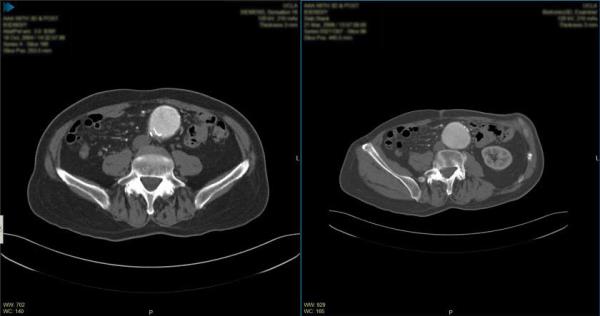

Side-by-side series comparison (study layout)